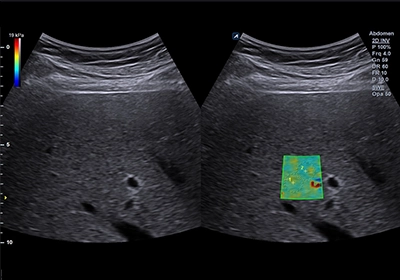

- B型肝炎以及C型肝炎因為慢性的發炎讓患者的肝臟逐步的纖維化但因為沒有任何的癥狀所以患者以及醫師便無法了解患者本身纖維化的程度甚至硬化的程度。肝炎帶原者若合併肝臟纖維化發生肝癌以及併發證的機率會顯著的上升。不論是超音波、核磁共振、或電腦斷層都無法正確判斷肝臟纖維化的程度,往往需要患者住院做肝切片的檢查才有辦法做較為正確的診斷。ARFI超音波的發明讓患者不要再做切片就能做診斷。經過國際醫學會證實ARFI超音波尤其是2D shear wave技術在各個方面對肝纖維化硬化的診斷都超過核磁共振以及電腦斷層。